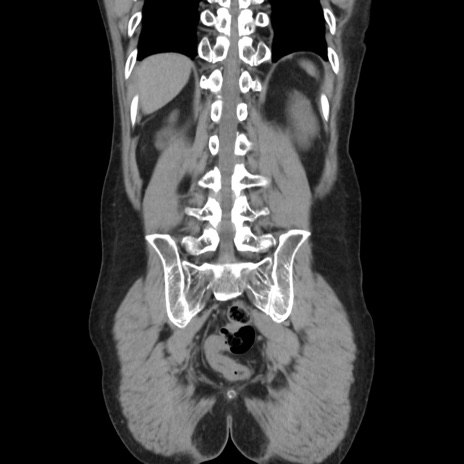

横断像